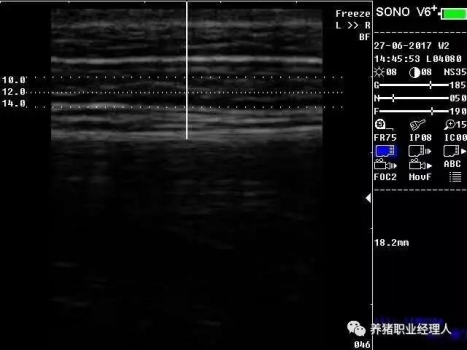

根據(jù)以上表格,活體測膘與實體測膘的相關(guān)分析及活體膘厚與胴體瘦肉率的相關(guān)分析結(jié)果證明,最后肋骨處和腰薦結(jié)合處離背中線5cm處(B5、C5)可作為活體測膘的最佳部位。 根據(jù)中華人民共和國農(nóng)業(yè)行業(yè)標(biāo)準(zhǔn)(NY/822-2004)種豬生產(chǎn)性能測定規(guī)程規(guī)定:生產(chǎn)性能背膘值運(yùn)用A超儀器測量的需測定腰薦椎結(jié)合處(P1)、胸腰椎結(jié)合處(P2)距背中線左側(cè)5cm處,兩點(diǎn)背膘厚平均值。生產(chǎn)性能背膘值運(yùn)用B超儀器測量的需測定倒數(shù)第三和第四肋骨間距背中線左側(cè)5cm處背膘厚。 2.3 剔剪剪毛 因為超聲波是不能在空氣中傳播的,所以在利用儀器測量之前,先用剔剪剪去測定部位的豬毛,方便測量儀器探頭與豬皮膚的無縫接觸。剪毛面積一般為5cm×5cm左右。此時若皮膚死皮結(jié)痂較多,便可用溫水擦洗去痂。 2.4涂耦合劑 耦合劑是檢測儀探頭與豬皮膚之間的中間潤滑劑,作為超聲波從儀器發(fā)出到豬體表和從豬體表回到儀器的傳播介質(zhì)。所以耦合劑的作用是排除探頭與豬體表之間的空氣和作為超聲波傳播的介質(zhì)。它是準(zhǔn)確測定背膘所不能缺少的。 2.5 正確測量 因為豬體表脂肪分為三層。所以不管是用A超還是B超,我們一般都能同時測量到三個數(shù)值,而正確反映豬只體況的是第三個數(shù)值。如圖所示:

測量時,盡量讓豬只安靜,避免豬只弓背或塌腰而使測量數(shù)據(jù)出現(xiàn)偏差。探頭應(yīng)直線平面與豬背正中線縱軸面垂直,不可斜切。同時探頭應(yīng)與豬背密接且不重壓。 2.6 讀取記錄數(shù)據(jù) 若為A超,讀取儀器亮三個指示燈時的數(shù)值,記錄下來。若為B超,觀察并調(diào)節(jié)屏幕影響,獲得理想影像時即凍結(jié)影像,測量背膘厚和眼肌面積,并加以說明標(biāo)記。影響打印或保存處理。 3、通過背膘測定指導(dǎo)豬生產(chǎn)飼喂管理 以妊娠母豬為例: 表3 妊娠母豬適宜背膘值范圍